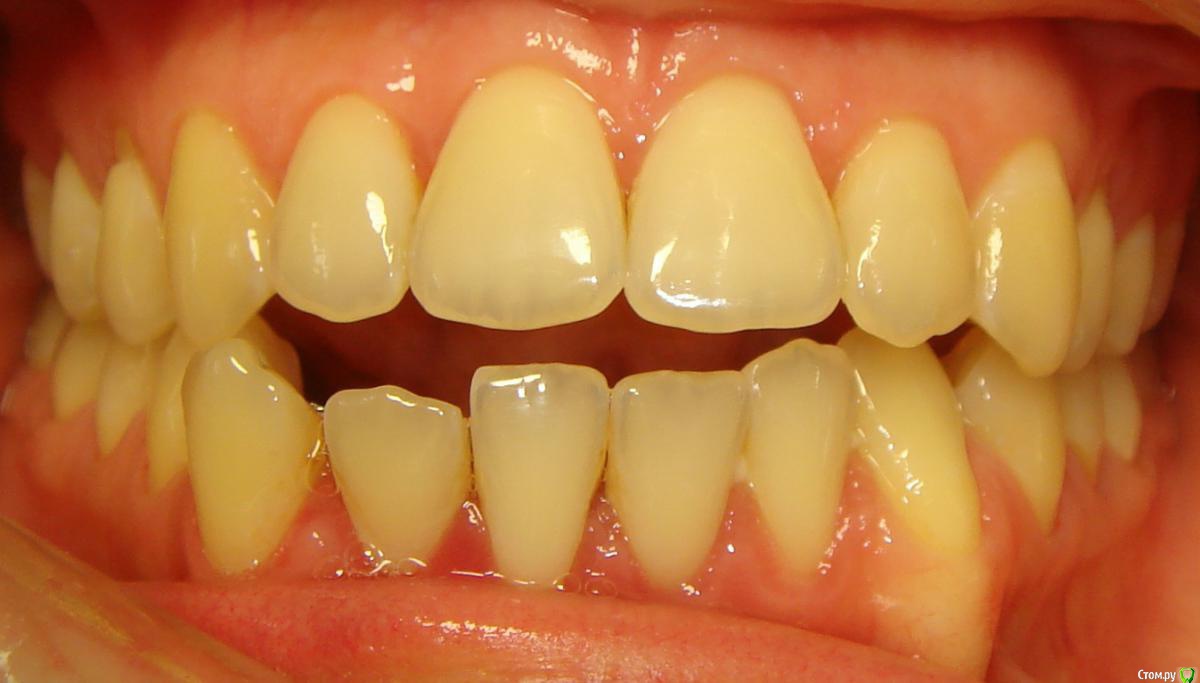

Opdihatop Опубликовано 4 марта, 2017 Поделиться Опубликовано 4 марта, 2017 И снова здравствуйте, коллеги. Вот такой вот случай к рассмотрению. Много лет назад пациентка уже проходила "камуфляжное" лечение. Со слов пациентки оно было закончено с передним открытым прикусом. Сейчас ситуация такая. Пациентка думает над ортохирургией, но меня смущает фронт н/ч. И по снимкам и по ситуации во рту корни 32, 31, 42, 43 зубов фенестрировали лингвальную кортикалку почти на всем протяжении, 33 - вестибулярную. Вопрос вот в чем: что делатьс этими зубами? Возможно ли их поставить на место? Или лучше не трогать, дольше простоят? Ссылка на комментарий

Brigita Опубликовано 4 марта, 2017 Поделиться Опубликовано 4 марта, 2017 она, кстати, везде язык прокладывает на фото. Наверно и в хирургии смысла не будет... Ссылка на комментарий